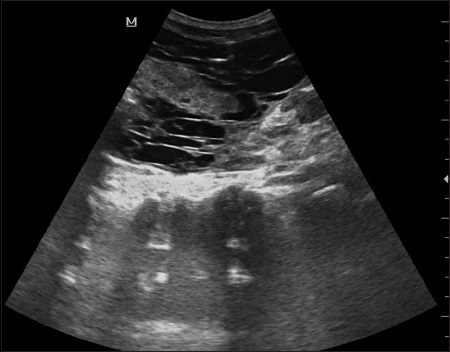

Normal ultrasound dimensions of newborn kidneys in Southwest Nigeria

Adejumoke I Ayede, Atinuke M Agunloye, Richard B Olatunji, Ibilola O Fawole, Ayodele S Jegede, Samuel I Omokhodion (Author)

128-134